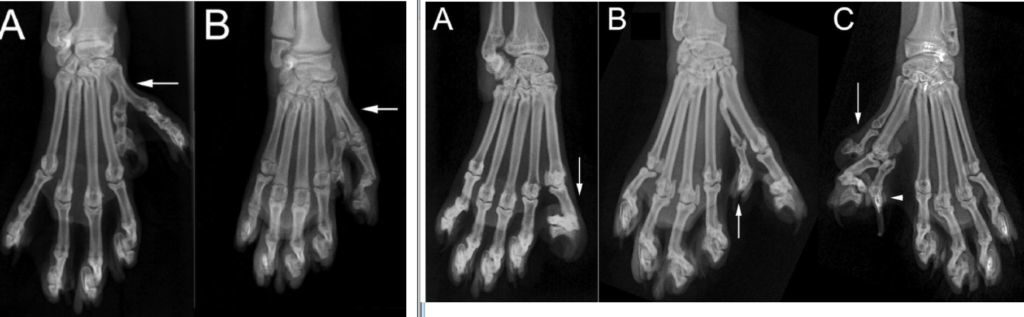

Обычно у кошек восемнадцать пальцев на лапах: по пять на передних и по четыре на задних лапах. Нередко котята крупных пород, например, мейн-кун и пиксибоб, рождаются с полидактилией только на передних или на передних и на задних лапах. Мутация является пороком, хотя любители мяукающих питомцев считают её отличительной особенностью.

В целом, полидактилия безболезненна, не доставляет дискомфорта животному, если пальцы развиты нормально. Кстати, за счёт дополнительных пальцев лапы большого размера, они широкие и благодаря этому, кошки легко передвигаются по сугробам, не проваливаясь в снег.

У некоторых особей дополнительные пальцы растут сбоку, как большой палец у человека. За счёт чего лапа становится похожа на варежку. Владельцы таких кошек утверждают, что при помощи боковых пальчиков питомцы ловко открывают задвижки дверей, шкафчиков и окна.

Полидактилией называется анатомическое отклонение, передающееся по наследству. При подобной генетической аномалии у котов наблюдаются лишние пальцы, количество которых может быть практически любым. Они располагаются сбоку, подобно большому пальцу человека, или вровень с основными.

Первый вариант носит название преаксиальная полидактилия, а владельцы ласково говорят, что у их питомцев «лапы-варежки». Если же речь идет о лишних пальцах, растущих вровень с остальными, данная аномалия называется постаксиальная полидактилия. А о таких кошках говорят, что у них «лапы-снегоступы». Оба состояния считаются вариантом нормы, поскольку не доставляют животным дискомфорта и не осложняют их жизнь.

Обычный котенок имеет восемнадцать пальцев. Десять из них расположены на передних лапах, а восемь – на задних. Но если у кого-то из родителей наблюдалась полидактилия, хотя бы один детеныш обязательно унаследует ее. Аномалия может проявляться у животных разных полов и пород. Чаще всего дополнительные пальцы вырастают на передних лапах или на передних и задних одновременно. Случаи, когда у кошки видоизменены только задние лапы, очень редки.